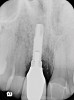

Figure 7  Radiograph depicting loss of supporting bone around the implant.

Figure 7